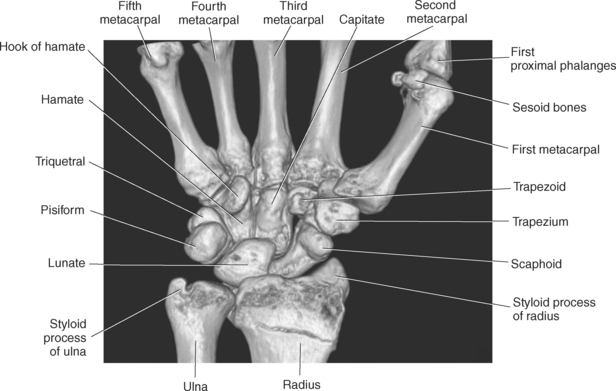

The bony anatomy of the wrist and hand consists of the distal radius and ulna, 8 carpal bones, 5 metacarpals, and 14 phalanges (Figure 9.101). Both the distal radius and ulna have a conical styloid process that acts as an attachment site for ligaments. The radial styloid process is located on the lateral surface of the radius, whereas the ulnar styloid process is located on the posteromedial side of the ulna. The carpal bones are arranged in proximal and distal rows. Located in the proximal row of carpal bones are the scaphoid (navicular), lunate (semilunar), triquetral (triquetrum), and pisiform bones. The pisiform is considered a sesamoid bone that is embedded in the tendon of the flexor carpi ulnaris. The distal row consists of the trapezium (greater multangular), trapezoid (lesser multangular), capitate (os magnum), and hamate (unciform) bones (Figures 9.102 through 9.114). The five metacarpals are small tubular bones with a proximal end (base), distal end (head), and shaft (body). The 14 phalanges that make up the fingers are short tubular bones. Like the metacarpals, each phalanx consists of a proximal (base), middle (body or diaphysis), and distal (head) portion. Each digit consists of 3 phalanges (proximal, middle, and distal), except for the thumb (first digit), which has only 2 phalanges (proximal and distal). The articulation of the phalanges of the second through fifth digits creates three interphalangeal joints: the metacarpophalangeal (MCP) joints classified as condyloid joints, proximal interphalangeal (PIP), and distal interphalangeal (DIP). The proximal and distal interphalangeal joints are classified as hinge joints (Figure 9.101). The first digit, which consists of 2 phalanges, has just two joints: the MCP joint, classified as a saddle joint, and an interphalangeal joint, classified as a hinge joint (Figure 9.101).

The joints of the wrist and hand are quite complex and consist of the following: distal radioulnar articulation, radiocarpal articulation (proximal joint of hand), midcarpal articulation (distal joint of hand), intercarpal articulations (articulations between proximal and distal carpals), carpometacarpal articulations (between carpals and metacarpals), the intermetacarpal articulations (between bases of metacarpals two through five) and the interphalangeal joints (between phalanges of each digit) (Figures 9.111 and 9.115). The distal radioulnar articulation, also called the distal radioulnar joint (DRUJ), is created when the ulnar notch of the radius moves around the articular circumference of the ulna, providing the movements of supination and pronation. The main stabilizing element of the DRUJ is an articular disk called the triangular fibrocartilage complex (TFCC). The TFCC is a fan-shaped band of fibrous tissue that originates on the medial surface of the distal radius and traverses horizontally to insert on the ulnar styloid process (Figures 9.115 and 9.116). It rotates against the distal surface of the ulnar head during pronation and supination and separates the ulna from the carpal bones. The proximal surface of the radiocarpal articulation is formed by the articular carpal surface of the radius and the TFCC, whereas the distal surface is formed by the articular surfaces of the scaphoid, lunate, and triquetrum and the interosseous ligaments connecting them (Figures 9.111 through 9.115). The midcarpal joint is formed by the articulations between the proximal and distal carpal rows (Figures 9.110 and 9.115). The articulation between the carpals within each row creates the intercarpal joints (Figures 9.111 and 9.115). The carpometacarpal joints are formed by the articulations between the carpus and the five metacarpals (Figure 9.111 and 9.115). The carpometacarpal joint of the thumb is an independent joint formed by the articular surfaces of the trapezium and first metacarpal, creating a pure saddle joint. The carpometacarpal articulations of the two to five digits are amphiarthrotic joints with little mobility (Figures 9.105 and 9.115). The intermetacarpal articulation exists between the base of the metacarpals and is joined by the palmar and dorsal metacarpal ligaments (Figure 9.115).